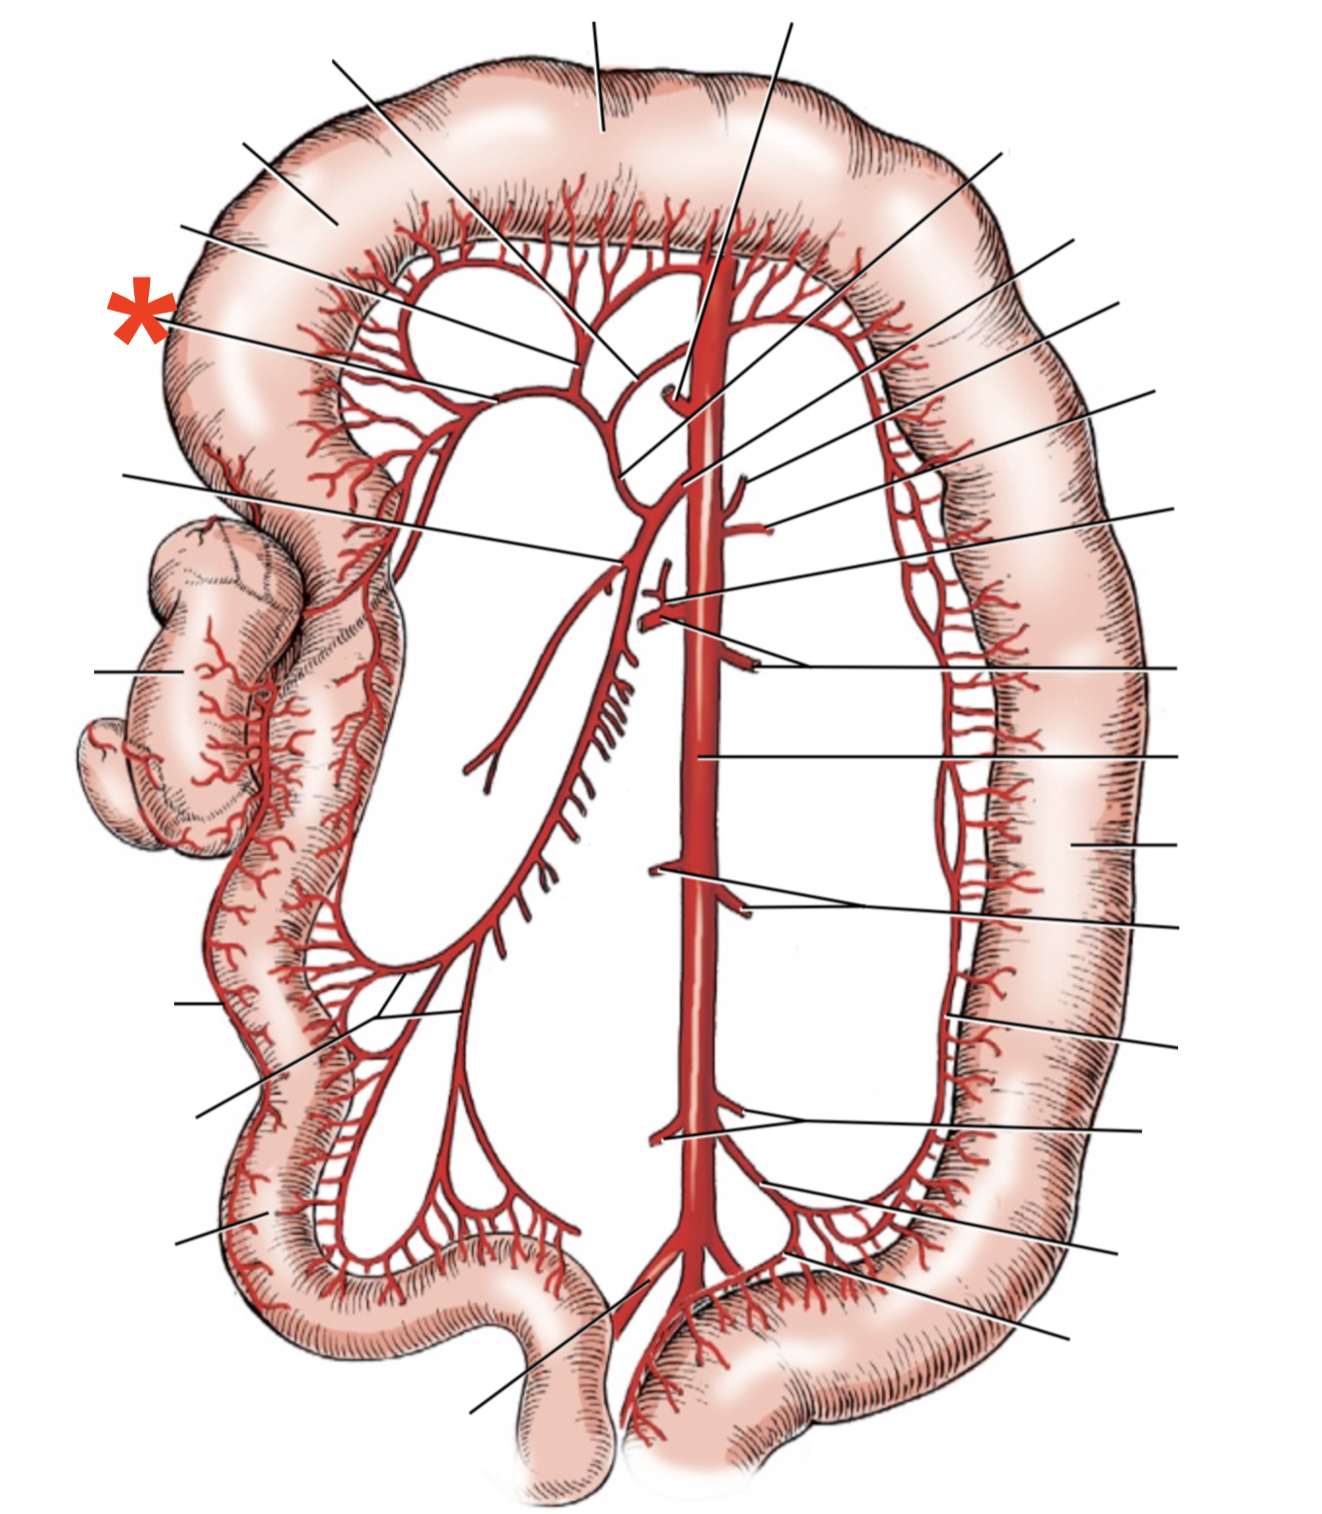

13

Q

A

A. mesenterica cranialis

15

Q

A

A. pancreaticoduodenalis caudalis

16

Q

A

Aa. jejunales

17

Q

A

A. ilei

- Anastomises with r. ileus mesenterialis a. iliocolica

18

Q

A

A. ileocolica

19

Q

A

A. colica dextra

20

Q

A

A. colica media

21

Q

A

A. mesenterica caudalis

22

Q

A

A. colica sinistra

23

Q

A

A. rectalis cranialis

List the branching of *a.* *mesenterica* *caudalis*

* *A. colica sinistra*

* *A. rectalis cranialis*

List the branches of *a.* *mesenterica* *cranialis*

* *A.* *pancreaticoduodenalis* *caudalis*

* *Aa. jejunalis*

* *A. ilei*

* Common trunk

* A. colica media

* A. colica dextra

* *A. ileocolica*

* *R. ilei mesenterialis*

* *A. cecalis*

* *R. colicus*